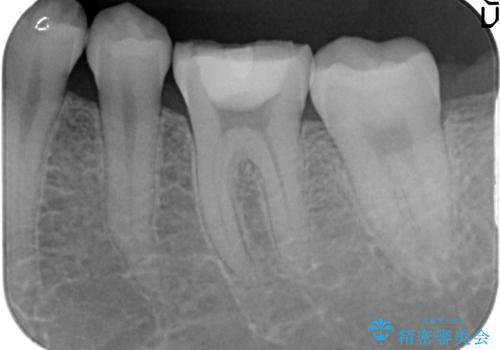

- 他院にて左下6番目の歯の根管治療を行っていたが、痛みが引かず抜歯を提案されたため、何とか歯を残せないかと当院にいらっしゃった方の症例です。

顕微鏡下で精密根管治療を行い、症状の緩解を確認後、オールセラミッククラウンによる補綴を行いました。